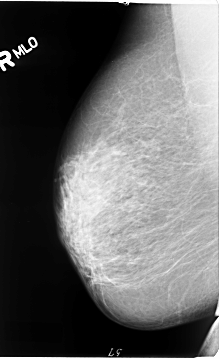

B_3064_1.RIGHT_MLO

RIGHT_MLO LINES 4664 PIXELS_PER_LINE 2856 BITS_PER_PIXEL 12 RESOLUTION 50 NON_OVERLAY